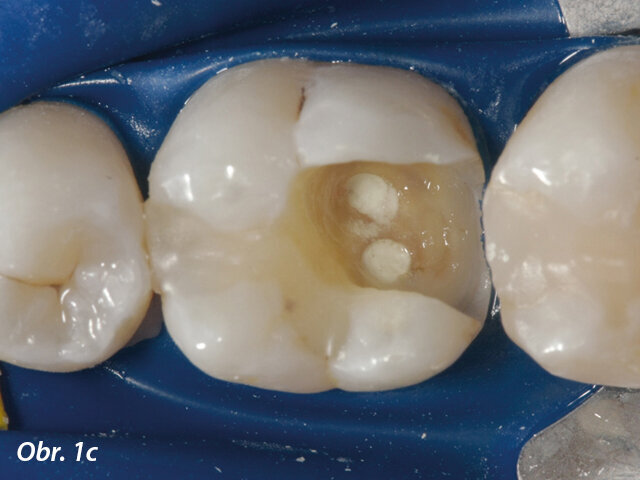

V posledních letech se stala populární terapie zachování vitální pulpy. Běžným materiálem pro překrytí pulpy byl hydroxid vápenatý, ale MTA vykazuje lepší výsledky v biokompatibilitě a úspěšnosti (Aguilar a Linsuwanont 2011). Případy s rozsáhlým kariézním nálezem mohou být úspěšně ošetřeny částečnou pulpotomií a překrytím MTA, což zachová pulpu vitální (obr. 1a–e).

Aplikace MTA s MAP systémem a PD MTA White

Aplikace PD MTA White s MAP systémem

Kondenzace MTA papírovým čepem